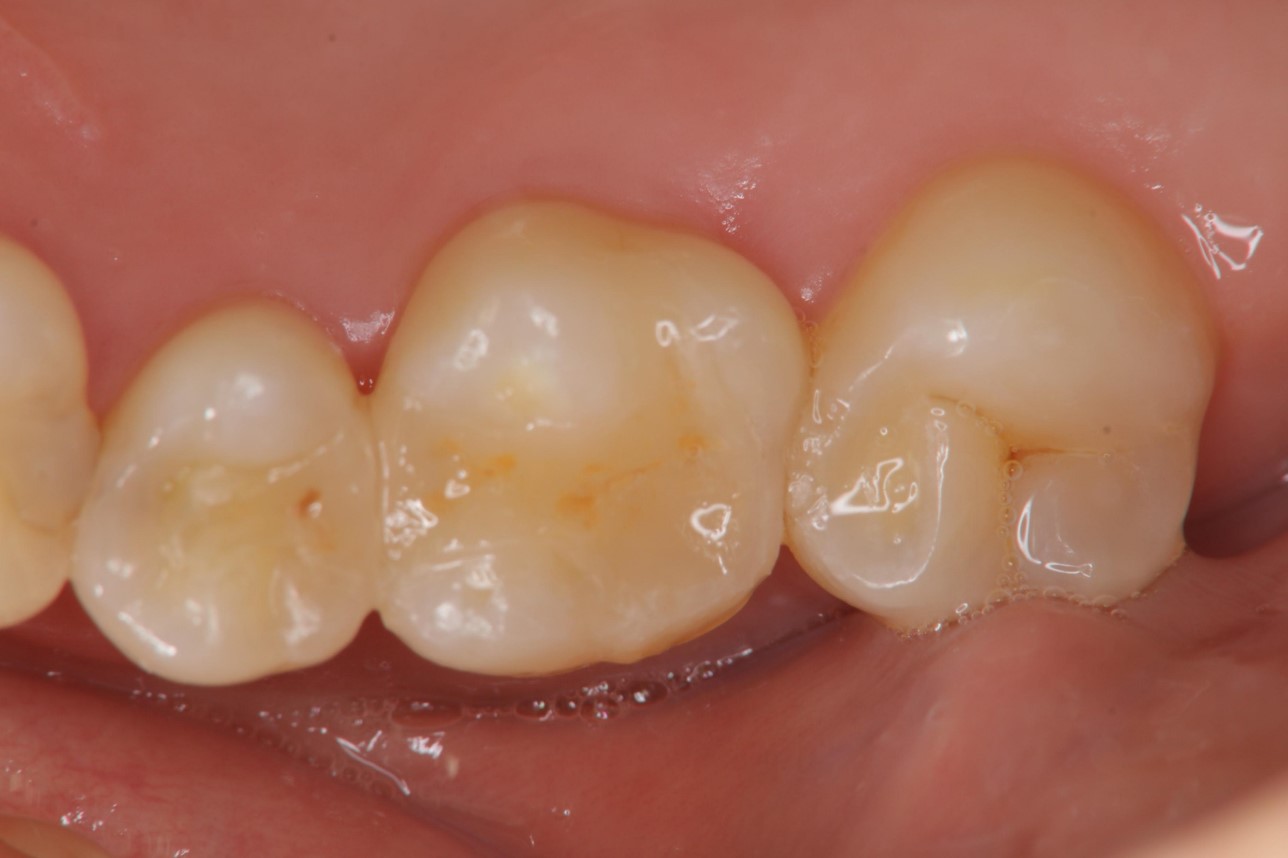

治療前,小臼齒與大臼齒之間冷熱敏感

小臼齒與大臼齒的陶瓷崁體